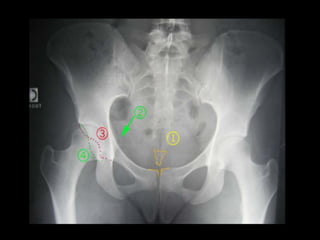

LA CEINTURE PELVIENNE

• Formé par : - sacrum

–os coxal ( au nombre de 2)

– OS COXAL:- Os antero-lateral de la ceinture pelvienne, il unit le

LA CEINTURE PELVIENNE •Formé par : - sacrum –os coxal ( au nombre de 2) – OS COXAL:- Os antero-lateral de la ceinture pelvienne, il unit le membres inférieurs au tronc